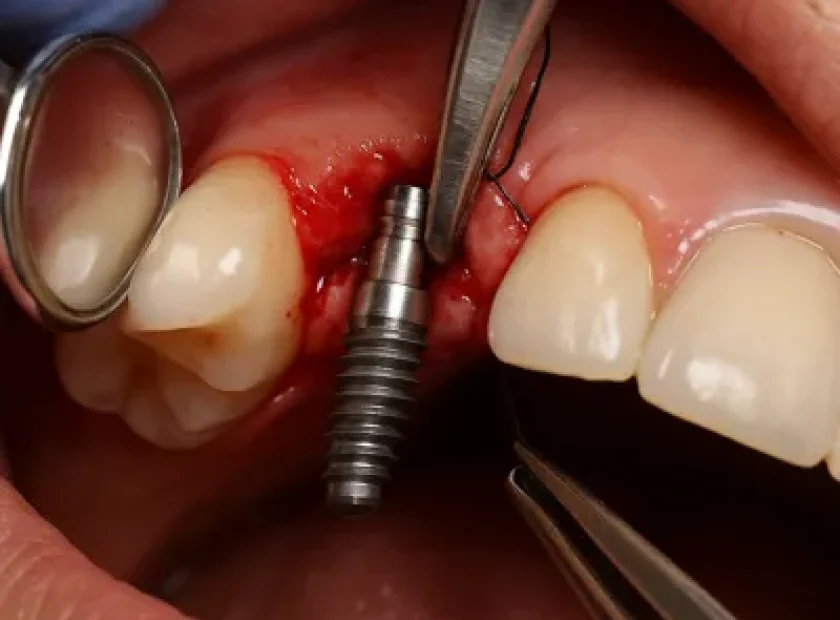

فاز جراحی ایمپلنت شامل تمام مراحلی می شود که طی آن ایمپلنت در داخل استخوان فک قرار داده می شود تا انجام فاز پروتزی تسهیل گردد. با اینکه فاز جراحی تنها یک مرحله از سلسله اقداماتی است که در نهایت منجر به ساخت یک پروتز متکی بر ایمپلنت می شود، اما این مرحله بسیار حیاتی است. چرا که نتایج موفقیت آمیز درمانی در گرو استحکام فیکسچر در داخل استخوان است.

قبل از انجام عمل جراحی بسیار مهم است که بیمار از کلیه مراحل درمانی آگاه شود تا سطح انتظاراتش را متناسب با محدودیت هایی که به لحاظ کلینیکی ممکن است پیش بیاید تنظیم نماید. هم چنین می بایست وضعیت کلینیکی بیمار از لحاظ انتخاب نوع جراحی و نیاز یا عدم نیاز به گرفت مورد بررسی قرار گیرد.

آزمایشات شامل معاینات خارج و داخل دهانی است. در طی این معاینات فاکتورهایی نظیر آسیمتری صورتی و خط لبخند بیمار و سایر فاکتورهای غیرطبیعی مورد بررسی قرار می گیرد. آزمایشات کلینیکی به صورت سیستماتیک انجام می شود و شامل آنالیز بافت نرم، پریودنشیوم (شامل بررسی بهداشت دهانی سلامت لثه ای، عمق پاکت ها)، دندان ها (شیری دائمی ترمیم شده یا غیر ترمیمی دریفت یا (Over Eruption و موقعیت دندان در اکلوژن (درهر دو وضعیت اینتر کاسپال و عقب رفته) و وجود یا عدم وجود پروتز می باشد.

همچنین محل دندان از دست رفته، میزان فضای موجود، وضعیت لثه در آن ناحیه می بایست مورد بررسی قرار گیرد. پس از اتمام این مراحل رادیوگرافی از بیمار گرفته می شود که ممکن است پانتوگرام (DPT) و یا عکس های پری اپیکال (PA) باشد. در اتمام این مرحله میزان مناسب بودن طرح درمان مبتنی بر ایمپلنت برای هر بیمار می بایست مدنظر قرار گیرد. تشخیص افتراقی به همراه بررسی پروگنوز دندان های باقیمانده انجام گرفته و در نهایت طرح درمان اولیه شکل می گیرد.